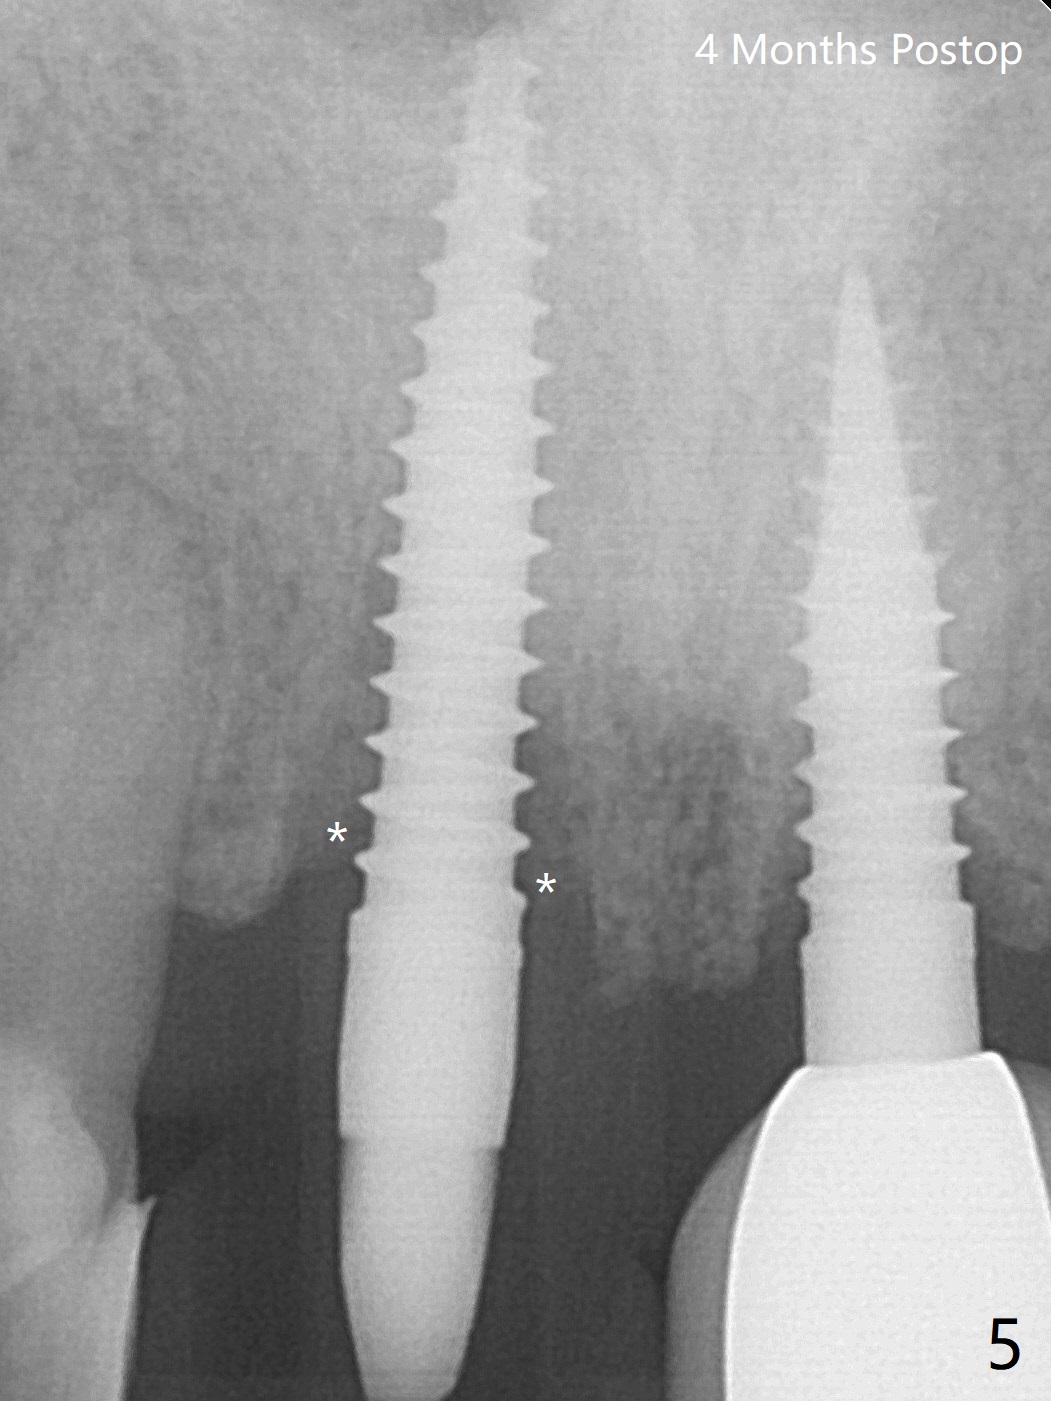

Reanalysis of preop CBCT shows a longer implant (3x16mm, green) to be placed palatal should be able to solve buccal plate bone loss associated with the previous 3x14 mm one at #8 (Fig.1). After crown/implant removal (with ease), a new palatal osteotomy is initiated flapless with 1.2 mm drill for 16 mm (palatal gingival margin, Fig.2). Following 1.5 mm drill for ~ 17 mm, a 3x16(2) mm 1-piece implant is placed >40 Ncm (Fig.3). After bone graft through limited access and abutment preparation, an immediate provisional is fabricated with clearance. The provisional dislodges repeatedly, mainly due to palatal perforation. It gets lost while the patient travels to his home country. Although there seems to be bone loss around the implant 2.5 months postop (Fig.4), the gingiva looks healthy. A new provisional is fabricated without impression. Because of short vertical height and small abutment diameter as well as bruxism, the provisional easily dislodges. The patient will return for impression 4 months 10 days postop. The bone loss remains 4 months postop when impression is taken (Fig.5).